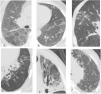

Early interstitial lung disease includes the following manifestations: septal thickening, reticulonodular opacities, ground glass opacities, mosaic appearance, emphysema, and cystic changes; while late manifestations include honey combing, tree in bud, crazy paving, consolidation, tractional bronchiectasis, and lung architecture distortion; Fig. 1. Study participants were divided into two groups based on the HRCT results, i.e., groups 1 (RA-ILD) and 2 (RA without ILD).

Typical MSCT findings of interstitial lung abnormalities. (A) Ground glass abnormalities, (B) reticular abnormalities with ground glass opacities, (C) tree in bud appearance, (D and E) traction bronchiectasis with reticulation and ground glass attenuation, and (F) honey combing demonstrated as clustered cystic air spaces.